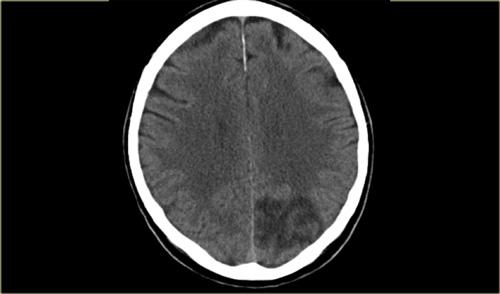

Bên trái là bệnh nhân bị mất thị lực cấp tính ở nửa phải của thị trường.

Hình ảnh CT cho thấy nhồi máu ở vỏ não thị giác đối bên, tức là thùy chẩm trái.

Chỉ khoảng 5% các trường hợp đột quỵ thiếu máu cục bộ liên quan đến PCA hoặc các nhánh của nó (3).

Bên trái là hình ảnh CT của bệnh nhân bị nhồi máu PCA.

Lưu ý sự mất phân biệt chất xám/chất trắng ở vùng thùy chẩm trái.